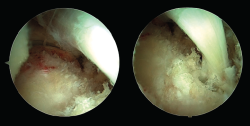

La sección del tendón FHL debe ser cuidadosa, con el objetivo de no poner en riesgo el paquete neurovascular tibial. La longitud mínima ideal del tendón FHL para su transposición al hueso calcáneo es de 15 mm. Antes de realizarse la sección del tendón, debe pasarse una sutura a su alrededor que permita con su tracción obtener la mayor longitud posible de tendón (Figura 2). Si al mismo tiempo de la tracción de la sutura se realiza una flexión plantar del tobillo y del hallux, aún se alcanzará mayor exposición del tendón, lo que permitirá conseguir mayor longitud del tendón.

Figura 2. Una sutura es pasada alrededor del tendón del flexor hallucis longus (FHL) para traccionarlo.

De acuerdo con las zonas descritas del tendón FHL(11), el tendón puede seccionarse en la zona 1 o 2. En la zona 1, el tendón se secciona justo antes de su entrada en la vaina fibro-ósea y con la ayuda de un bisturí o tijeras artroscópicas introducidas a través del portal endoscópico posterolateral. Alternativamente, el FHL puede seccionarse en su zona 2 a su paso bajo el sustentaculum tali. En este último caso, el artroscopio debe introducirse en la vaina fibro-ósea del tendón de FHL y, bajo visión artroscópica directa, el tendón se secciona con la ayuda de un bisturí de cirugía percutánea (bisturí de percutánea número 64) (Figura 3).

Figura 3. Sección del tendón flexor hallucis longus (FHL) en la zona 2. El artroscopio es introducido en la vaina fibro-ósea del tendón de FHL, el punto de sección es identificado con una aguja (visión superior), después es seccionado con un bisturí de cirugía percutánea (visión inferior).